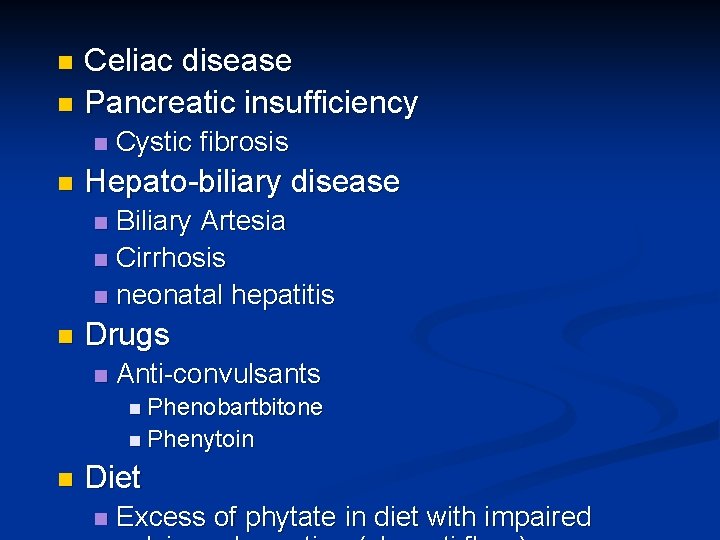

Celiac disease n Pancreatic insufficiency n n n Cystic fibrosis Hepato-biliary disease Biliary Artesia n Cirrhosis n neonatal hepatitis n n Drugs n Anti-convulsants n Phenobartbitone n Phenytoin n Diet n Excess of phytate in diet with impaired